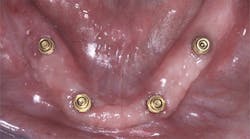

Overdenture supported by four conventional or small implants(Figures 5–6)

Commonly there is more bone in the anterior area of the mandible or maxilla than in the premolar and molar areas. The two previously described procedures discuss techniques placing the implants primarily in the anterior area. However, occasionally there is sufficient bone quantity and acceptable bone quality in the posterior area to place implants posterior to the mental foramen.

The following technique includes placing two implants in the canine areas and two implants in the posterior areas, preferably posterior to the mental foramen. The same principles described for the previous two techniques apply to this third technique. However, the cost to patients is usually higher.

Using 2013 average fees as reported by the ADA, the cost for the above technique for one new mandibular denture placed over four implants is:

Treatment | ADA Code | Average |

Four conventional or small diameter implants at $1,788 each or $760 each. If small diameter implants are used, they should be of the larger variety, such as 2.9 mm in diameter | D6010 or D6013 | $3,040 - $7,152 |

Four stock abutments such as Locators or ERAs at $630 each | D6056 | $2,520 |

One new complete denture | D5110 | $1,469 |

Total Cost of Treatment | $7,029 | |

(Fees vary, but this is a reasonable average based on the 2013 ADA survey data.)